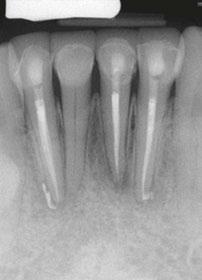

Evaluation of hard tissue quantity and quality (Figures 1 and 2) is a key diagnostic factor when determining potential sites for sufficient primary stability. The implant surgeon needs to be able to evaluate a patient’s CBCT to locate areas of hard tissue for dental implants to be placed in a prosthetically driven, mechanically fixed, and biologically stable position. This is done by identifying and evaluating the patient-specific variations of common anatomical structures such as the maxillary sinus, nasal aperture, neurovascular canals, and the bone density (classified as D1, D2, D3, or D4 bone by Misch). Common areas of bone used for full-arch immediately loaded implants in the maxilla include: the alveolar ridge and basal bone apical to extraction sockets, palatal

Figure 1 (left): Radiographic example of soft D4 bone. Figure 2 (right): Radiographic example of more dense D1/D2 bone